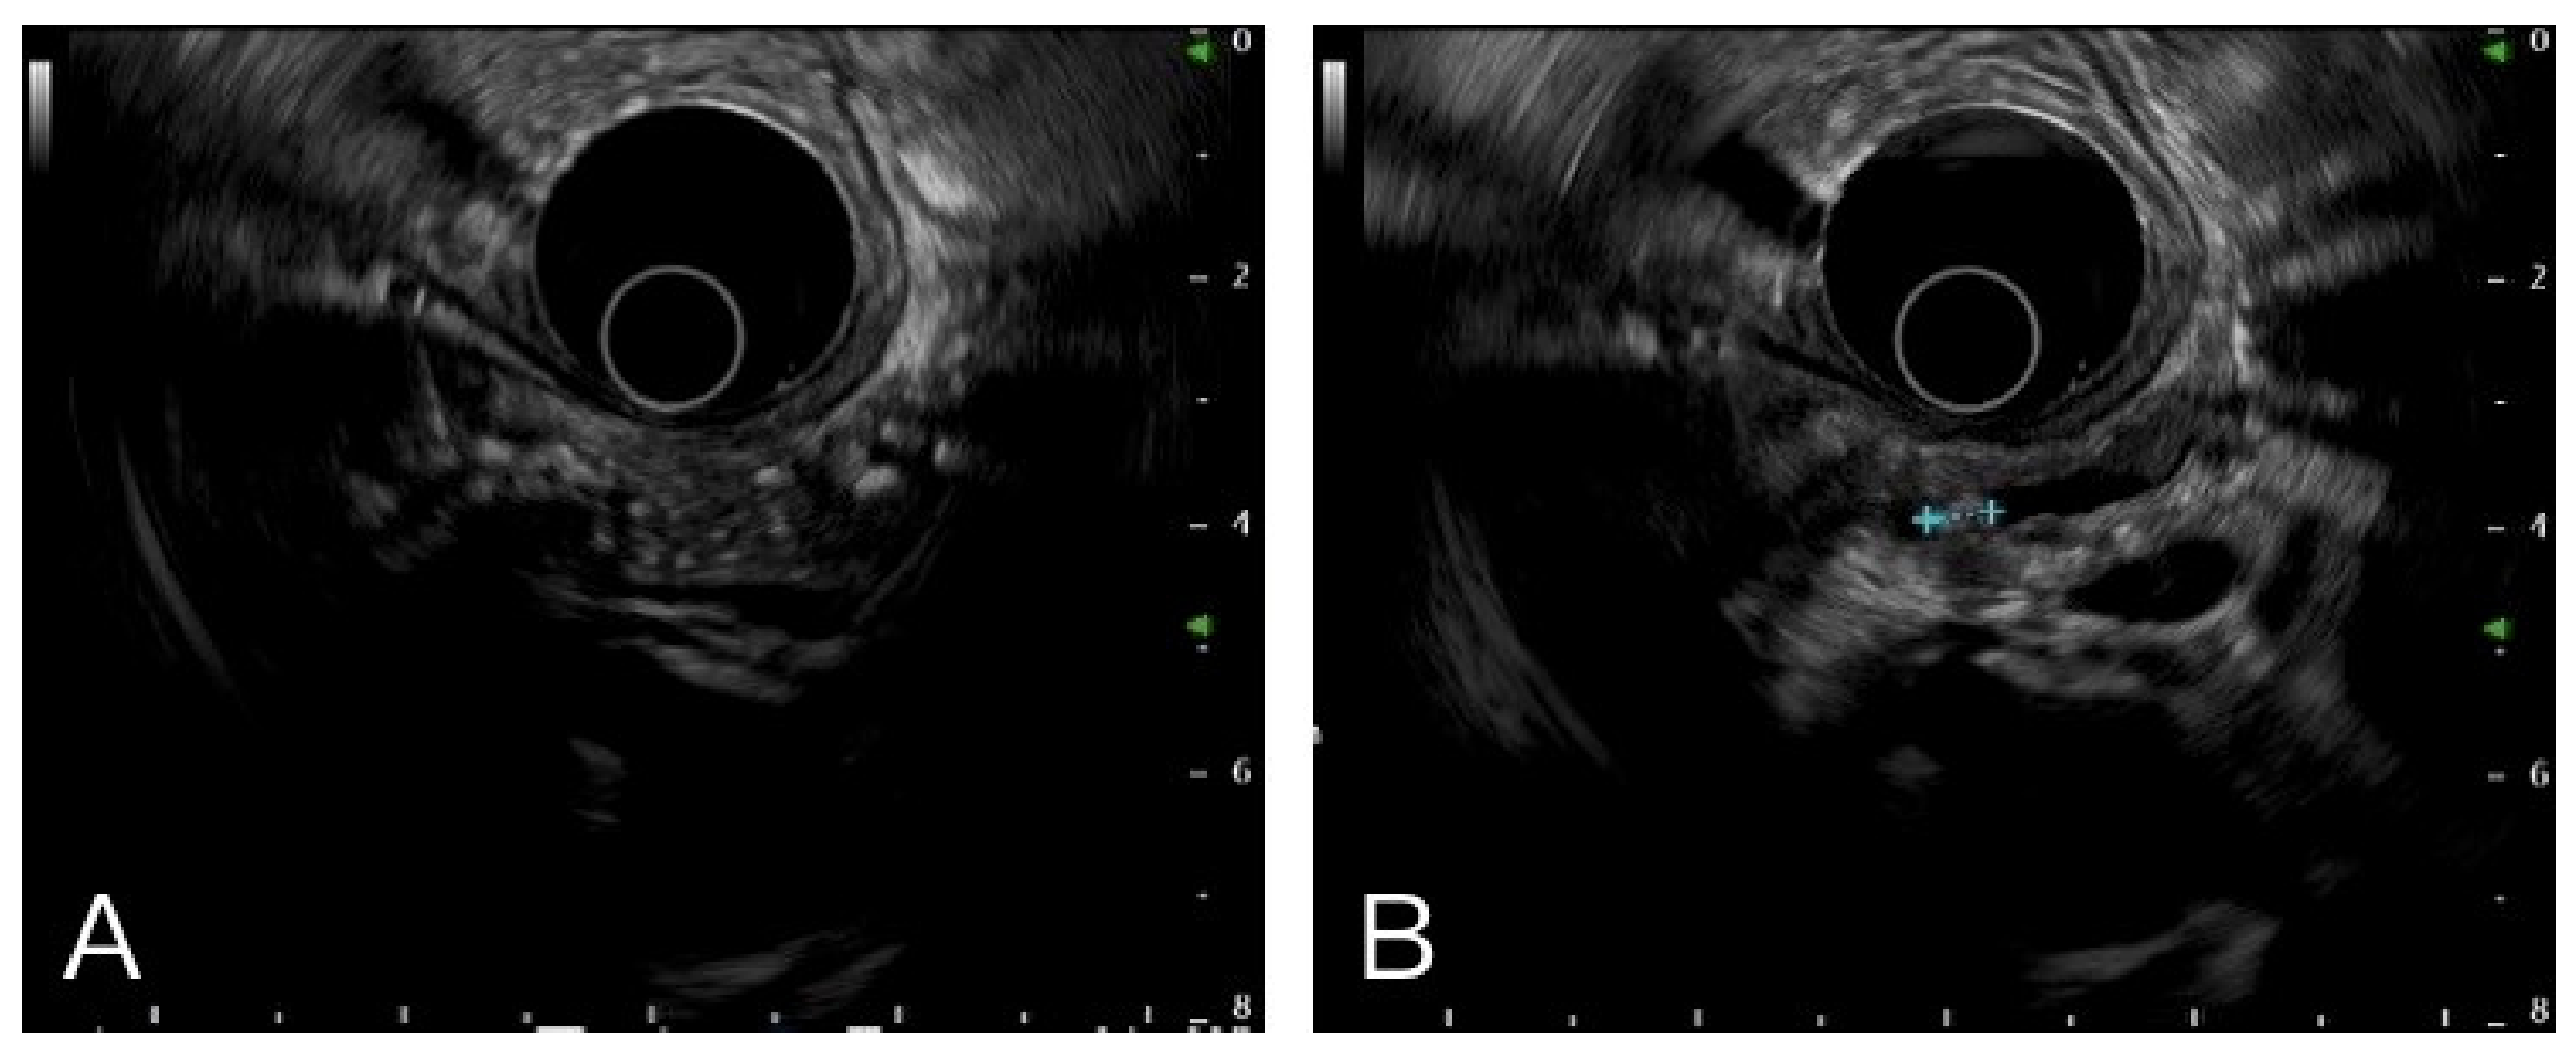

Figure 1.

Multiple hyperechoic foci with posterior acoustic shadow (A) and stone in pancreatic duct (B) were the typical images in chronic pancreatitis.